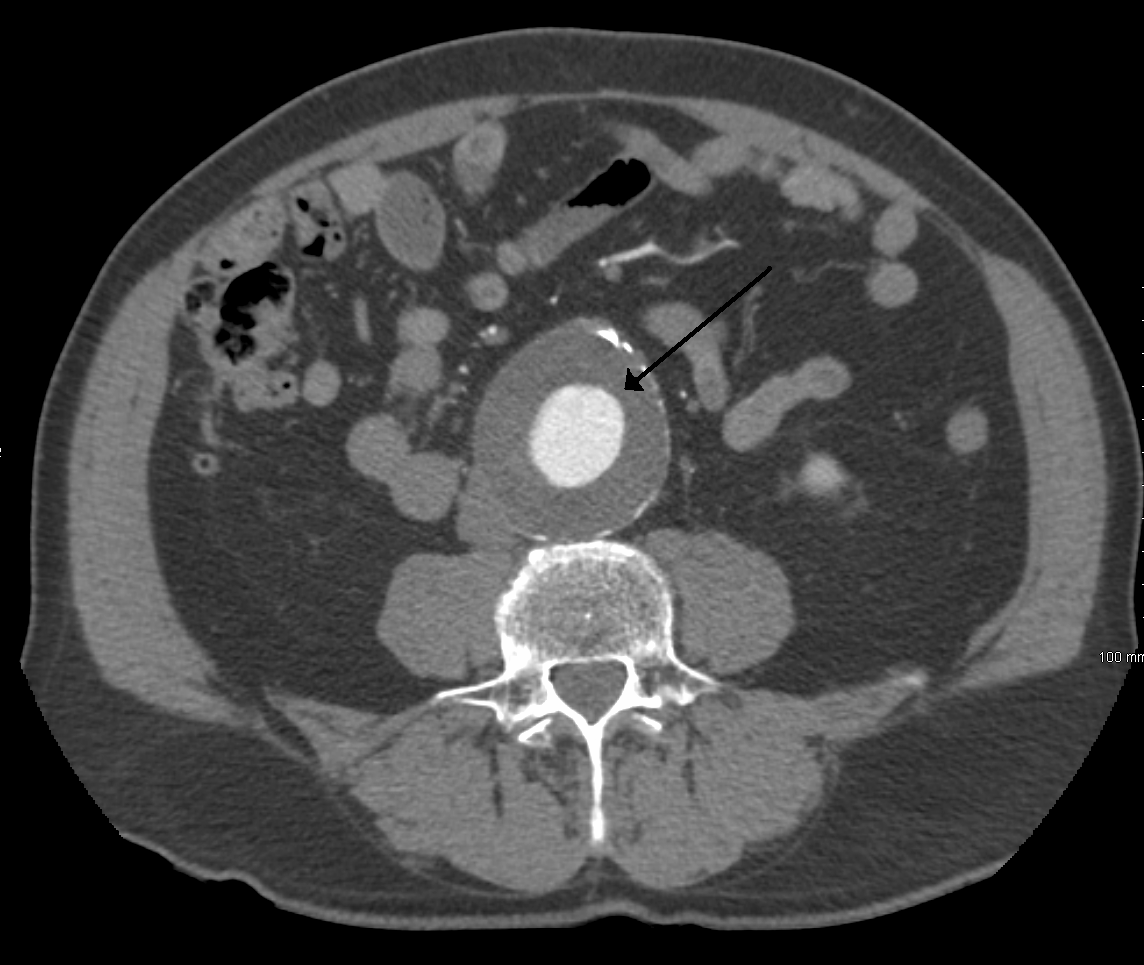

내경 3cm, 직경 6.5cm의 복부대동맥류

• 조영증강 복부 CT 스캔: AAA를 진단하고 치료 옵션을 결정하는 데 가장 좋은 검사이다.

복부 대동맥류(AAA)는 직경 3cm 이상 또는 정상 크기보다 50% 이상 확장된 경우를 말하며,[38] 미국에서는 흡연 경력이 있는 65~75세 남성에게 초음파 스크리닝이 권장되고 있으며,[43] 영국에서는 65세 이상 모든 남성에게 스크리닝이 권장된다.[38]